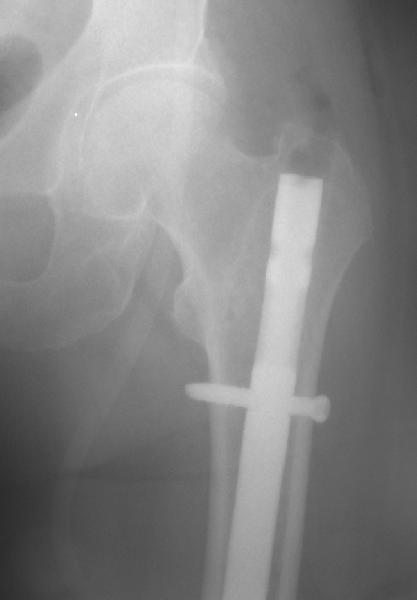

Отправитель: Alexander Chelnokov 20 Апрель 2011, 00:15

Больше 10 уже. Были 1 механическая неудача (сломалась очень тонкая ножка) и 1 глубокая инфекция.

Приходится индивидуально делать под конкретную ножку, с предпритием ЦИТО это получается за несколько дней и недорого.

Были пока только переломы и несращения. С деформациями как-то не попадались пока.

Нам каждый случай интересен, так что давай созвонимся-спишемся, возможно, получится что-то совместно сделать.